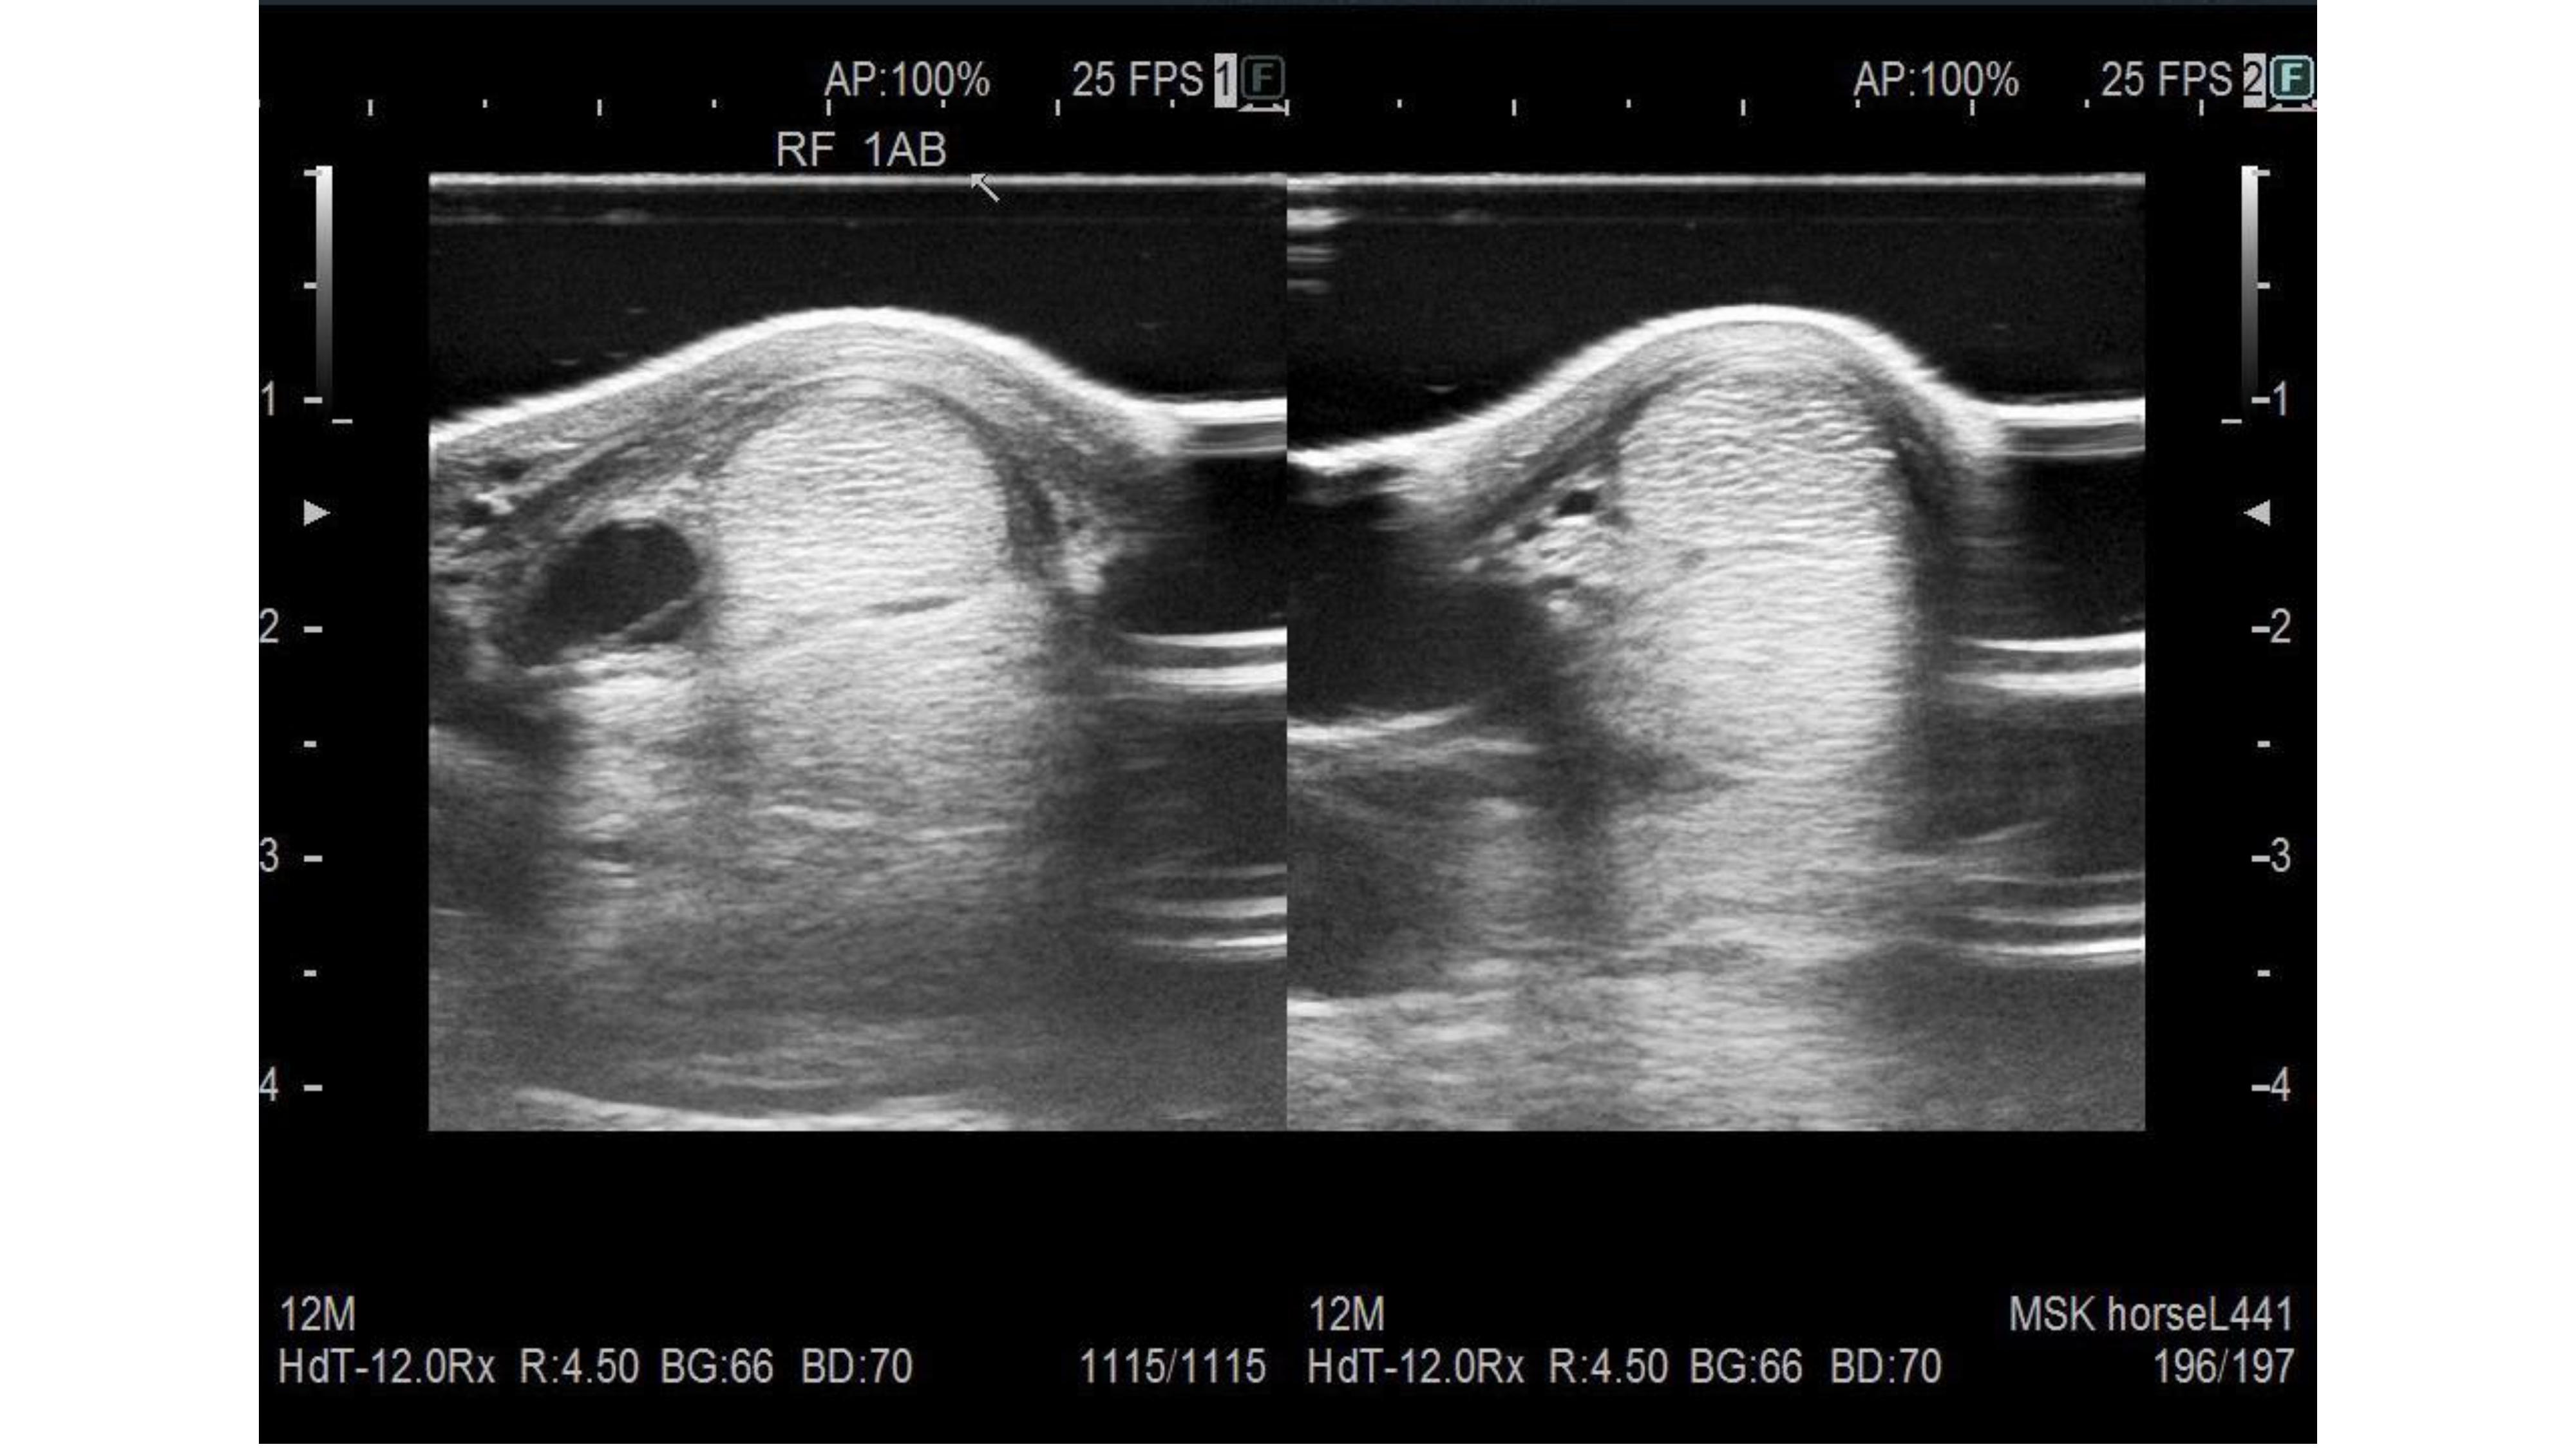

ZENITH(ゼニス)アーカイブ(生産終了、手配不可) - クロノマスター エル・プリメロ オープン | ブランド腕時計の正規販売店 A.M.I, ゲルズの21 セン2歳 ※育成馬 | サラブレッドオークション,

ゲルズの21 セン2歳 ※育成馬 | サラブレッドオークション, ZENITH(ゼニス)アーカイブ(生産終了、手配不可) - クロノマスター エル・プリメロ オープン | ブランド腕時計の正規販売店 A.M.I